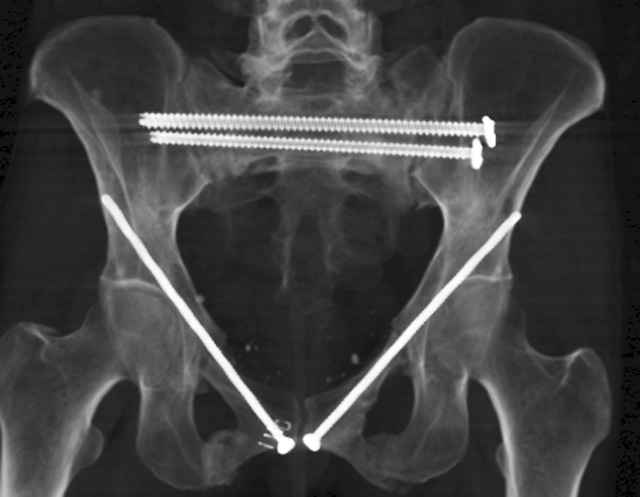

Here are a recent patient’s example slides...

54 yo Female Fell c/o Pain

Initial Films

?Instability on Exam - Limited by Pain

NonOp Initial Mgmt

3 Months After Fall

Continued Pain & Immobility

(+) Instability to Compressive Manual Exam

Percutaneous Fixation

(B) Ramus-Retrograde

2 TransIliac-TransSacral

Upper Segment